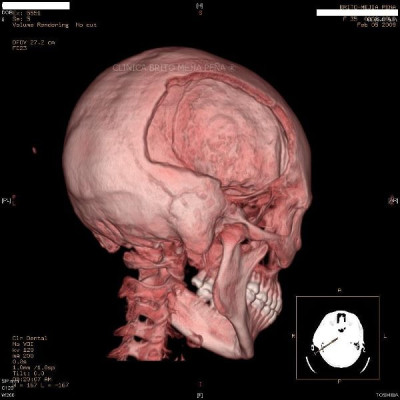

Cabeza y Cuello 2

Envíado por BMP Imágenes Diagnósticas

BMP Imágenes Diagnósticas